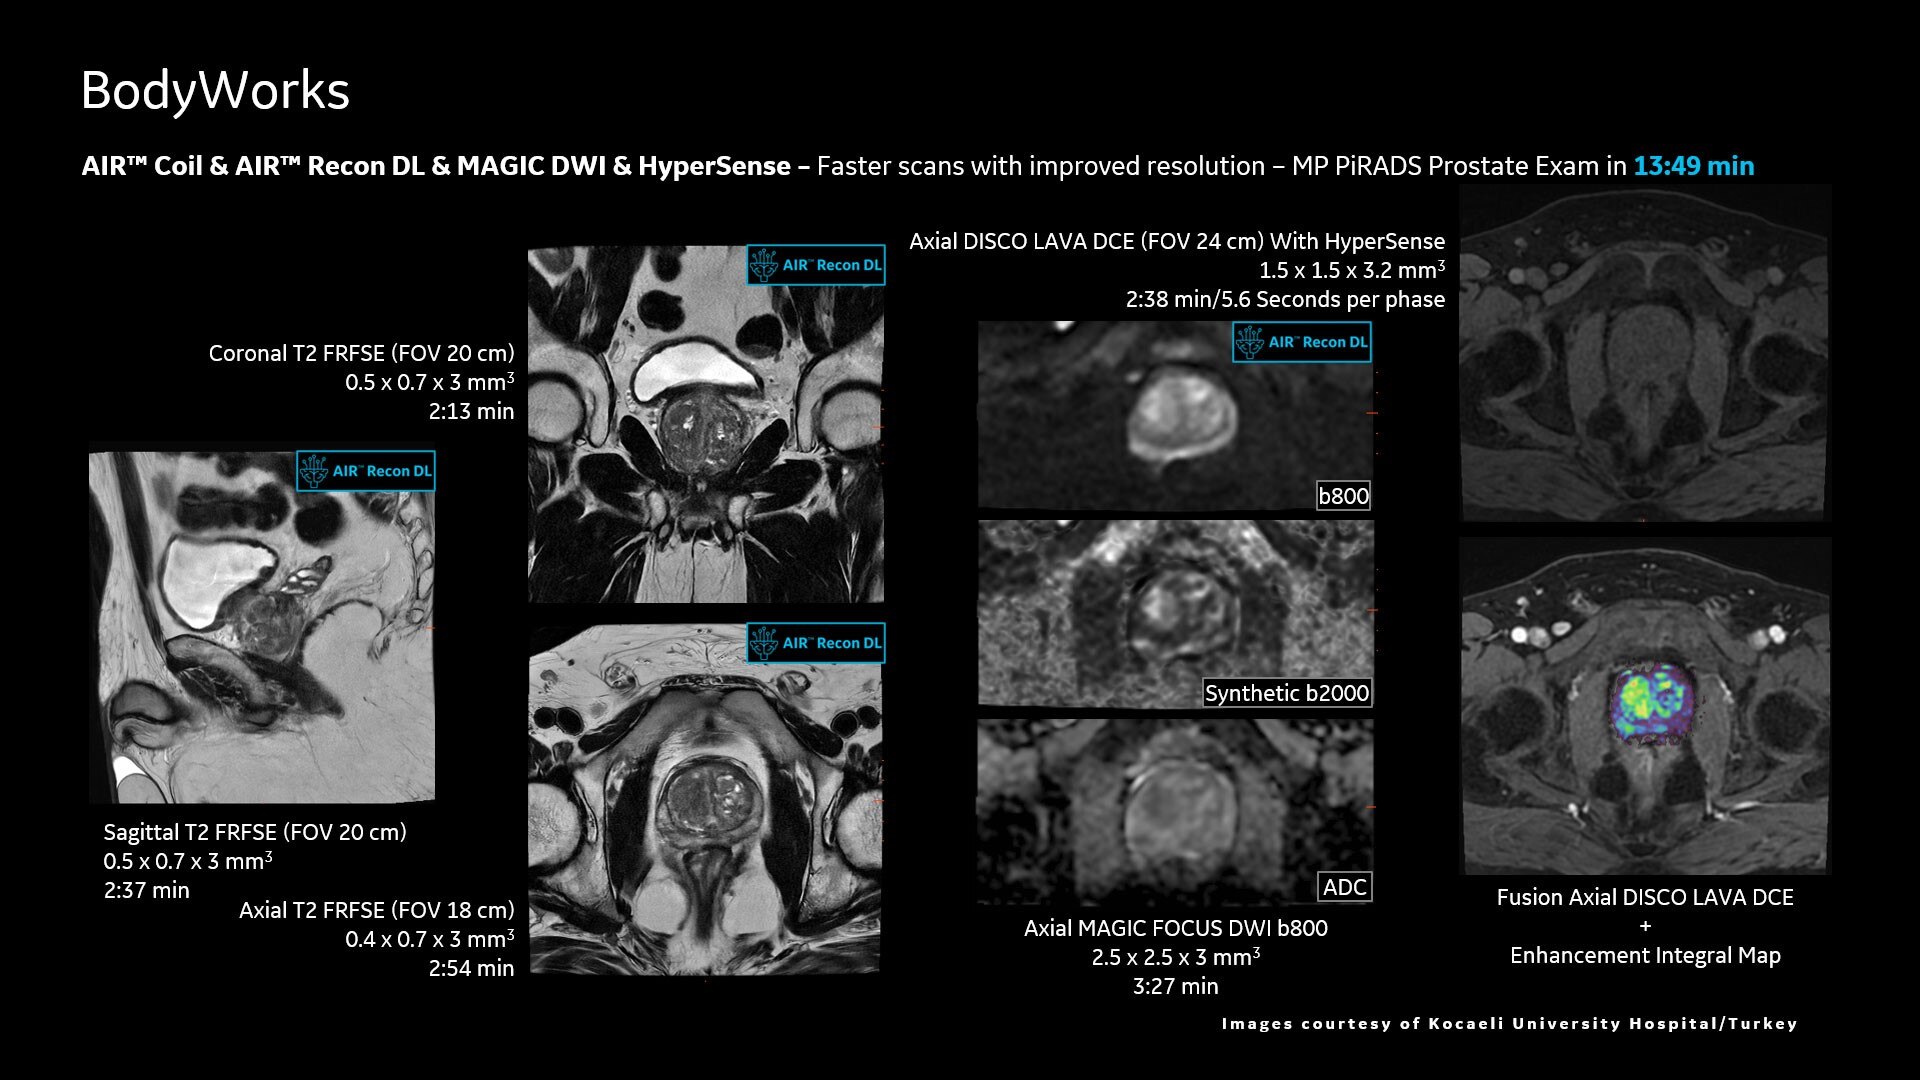

AIR™ Recon DL improves SNR and image sharpness, enabling shorter scan times

Up to 50% faster acquisition time with AIR™ Recon DL